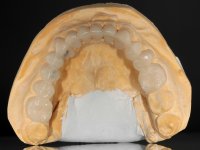

Avaliada a situação inicial em conjunto com o médico dentista, foi considerado prioritário alterar a forma dos dentes, subir 1.5mm a D.V.O. e descruzar a mordida do 1º Quadrante. Na confeção da ponte provisória superior de acrílico com reforço metálico foram já ensaiadas essas alterações. Optamos por um monobloco de 13 dentes com o intuito de manter a estabilidade posicional dos dentes re- preparados. Após remoção das coroas e pontes antigas foi feita a re-preparação dentária. A ponte provisória foi rebasada em boca, primeiro com acrílico auto-polimerizável e depois com resina composta. Após 4 semanas de integração da ponte provisória superior foi confecionada a ponte provisória inferior, corrigindo-se finalmente as discrepâncias existentes no plano oclusal. As impressões foram realizadas com a técnica de dupla mistura, com dupla mistura. Simultaneamente foram feitos os registos da relação inter-maxilar e da relação do maxilar superior com a base do crânio, utilizando o arco facial. Montados os modelos de trabalho em articulador semi-ajustável, foram confecionadas as peças próteticas, utilizando tecnologia CAD-CAM para a realização das infra-estruturas em zircónia. A colocação da cerâmica foi feita procurando que a forma dos dentes reproduzisse uma forma anatómica natural. A tonalidade foi condicionada pela vontade do paciente. Foi feita uma prova com a cerâmica em “biscuit” para verificação técnica e validação estética. Após aprovação pelo paciente o trabalho foi finalizado e colocado em boca.